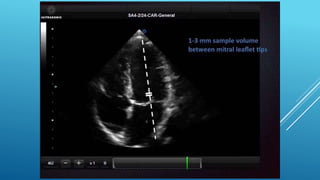

๏‚„ standard transthoracic echo (TTE) is typically

๏‚„ screening modality of choice for LV thrombus

๏‚„ detection and should performed within 24 hours

๏‚„ of admission in those at high risk for apical LV thrombus

๏‚„ (Large or anterior MI or receiving delayed reperfusion).

๏‚„ standard transthoracicecho (TTE) is typically ๏‚„ screening modality of choice for LV thrombus ๏‚„ detection and should performed within 24 hours ๏‚„ of admission in those at high risk for apical LV thrombus ๏‚„ (Large or anterior MI or receiving delayed reperfusion). ๏‚„ Contrast TTE or Cardiac MRI should be considered ๏‚„ based on local availability and resources. If .... ๏‚„ (1) LV apex is poorly visualized, ๏‚„ (2) Anterior or Apical wall motion abnormalities are present ๏‚„ (3) High Apical wall motion scores are calculated ๏‚„ (โ‰ฅ5 on noncontrast TTE)